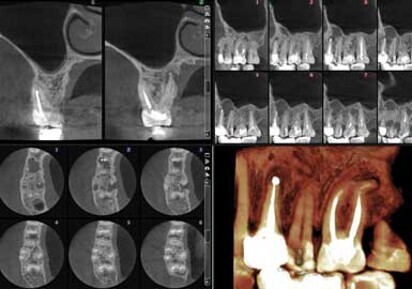

The ProMax 3Ds and 3D units from Planmeca are designed for capturing the smallest anatomical details with precision. High-resolution images with a 75 µm voxel size and efficient artifact removal make these units an ideal choice for effective case planning and precise diagnostic capabilities, according to the company.

Planmeca ARA artifact removal algorithm removes shadows and streaks from the 3-D image, such as those caused by metal and root fillings, according to Planmeca.

All ProMax units include Planmeca Romexis open-architecture software with versatile tools for endodontic diagnostic and treatment planning needs, such as true measurements and 3-D visualization of root canals. CBCT applications in endodontics include: